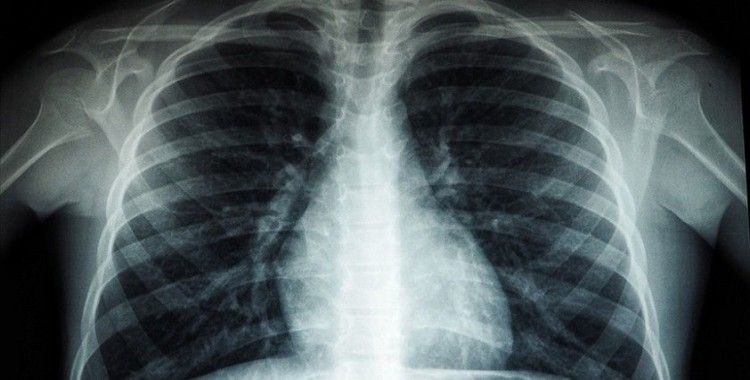

Röntgen ve ileri tetkiklerle hastalığın tespit edilebildiğinin altını çizen Özkara, Türkiye'de veremin 6 ay kullanılan ilaçlarla kolaylıkla tedavi edilebildiğine ve tüm tedavi masraflarının da devlet tarafından karşılandığına dikkati çekti.